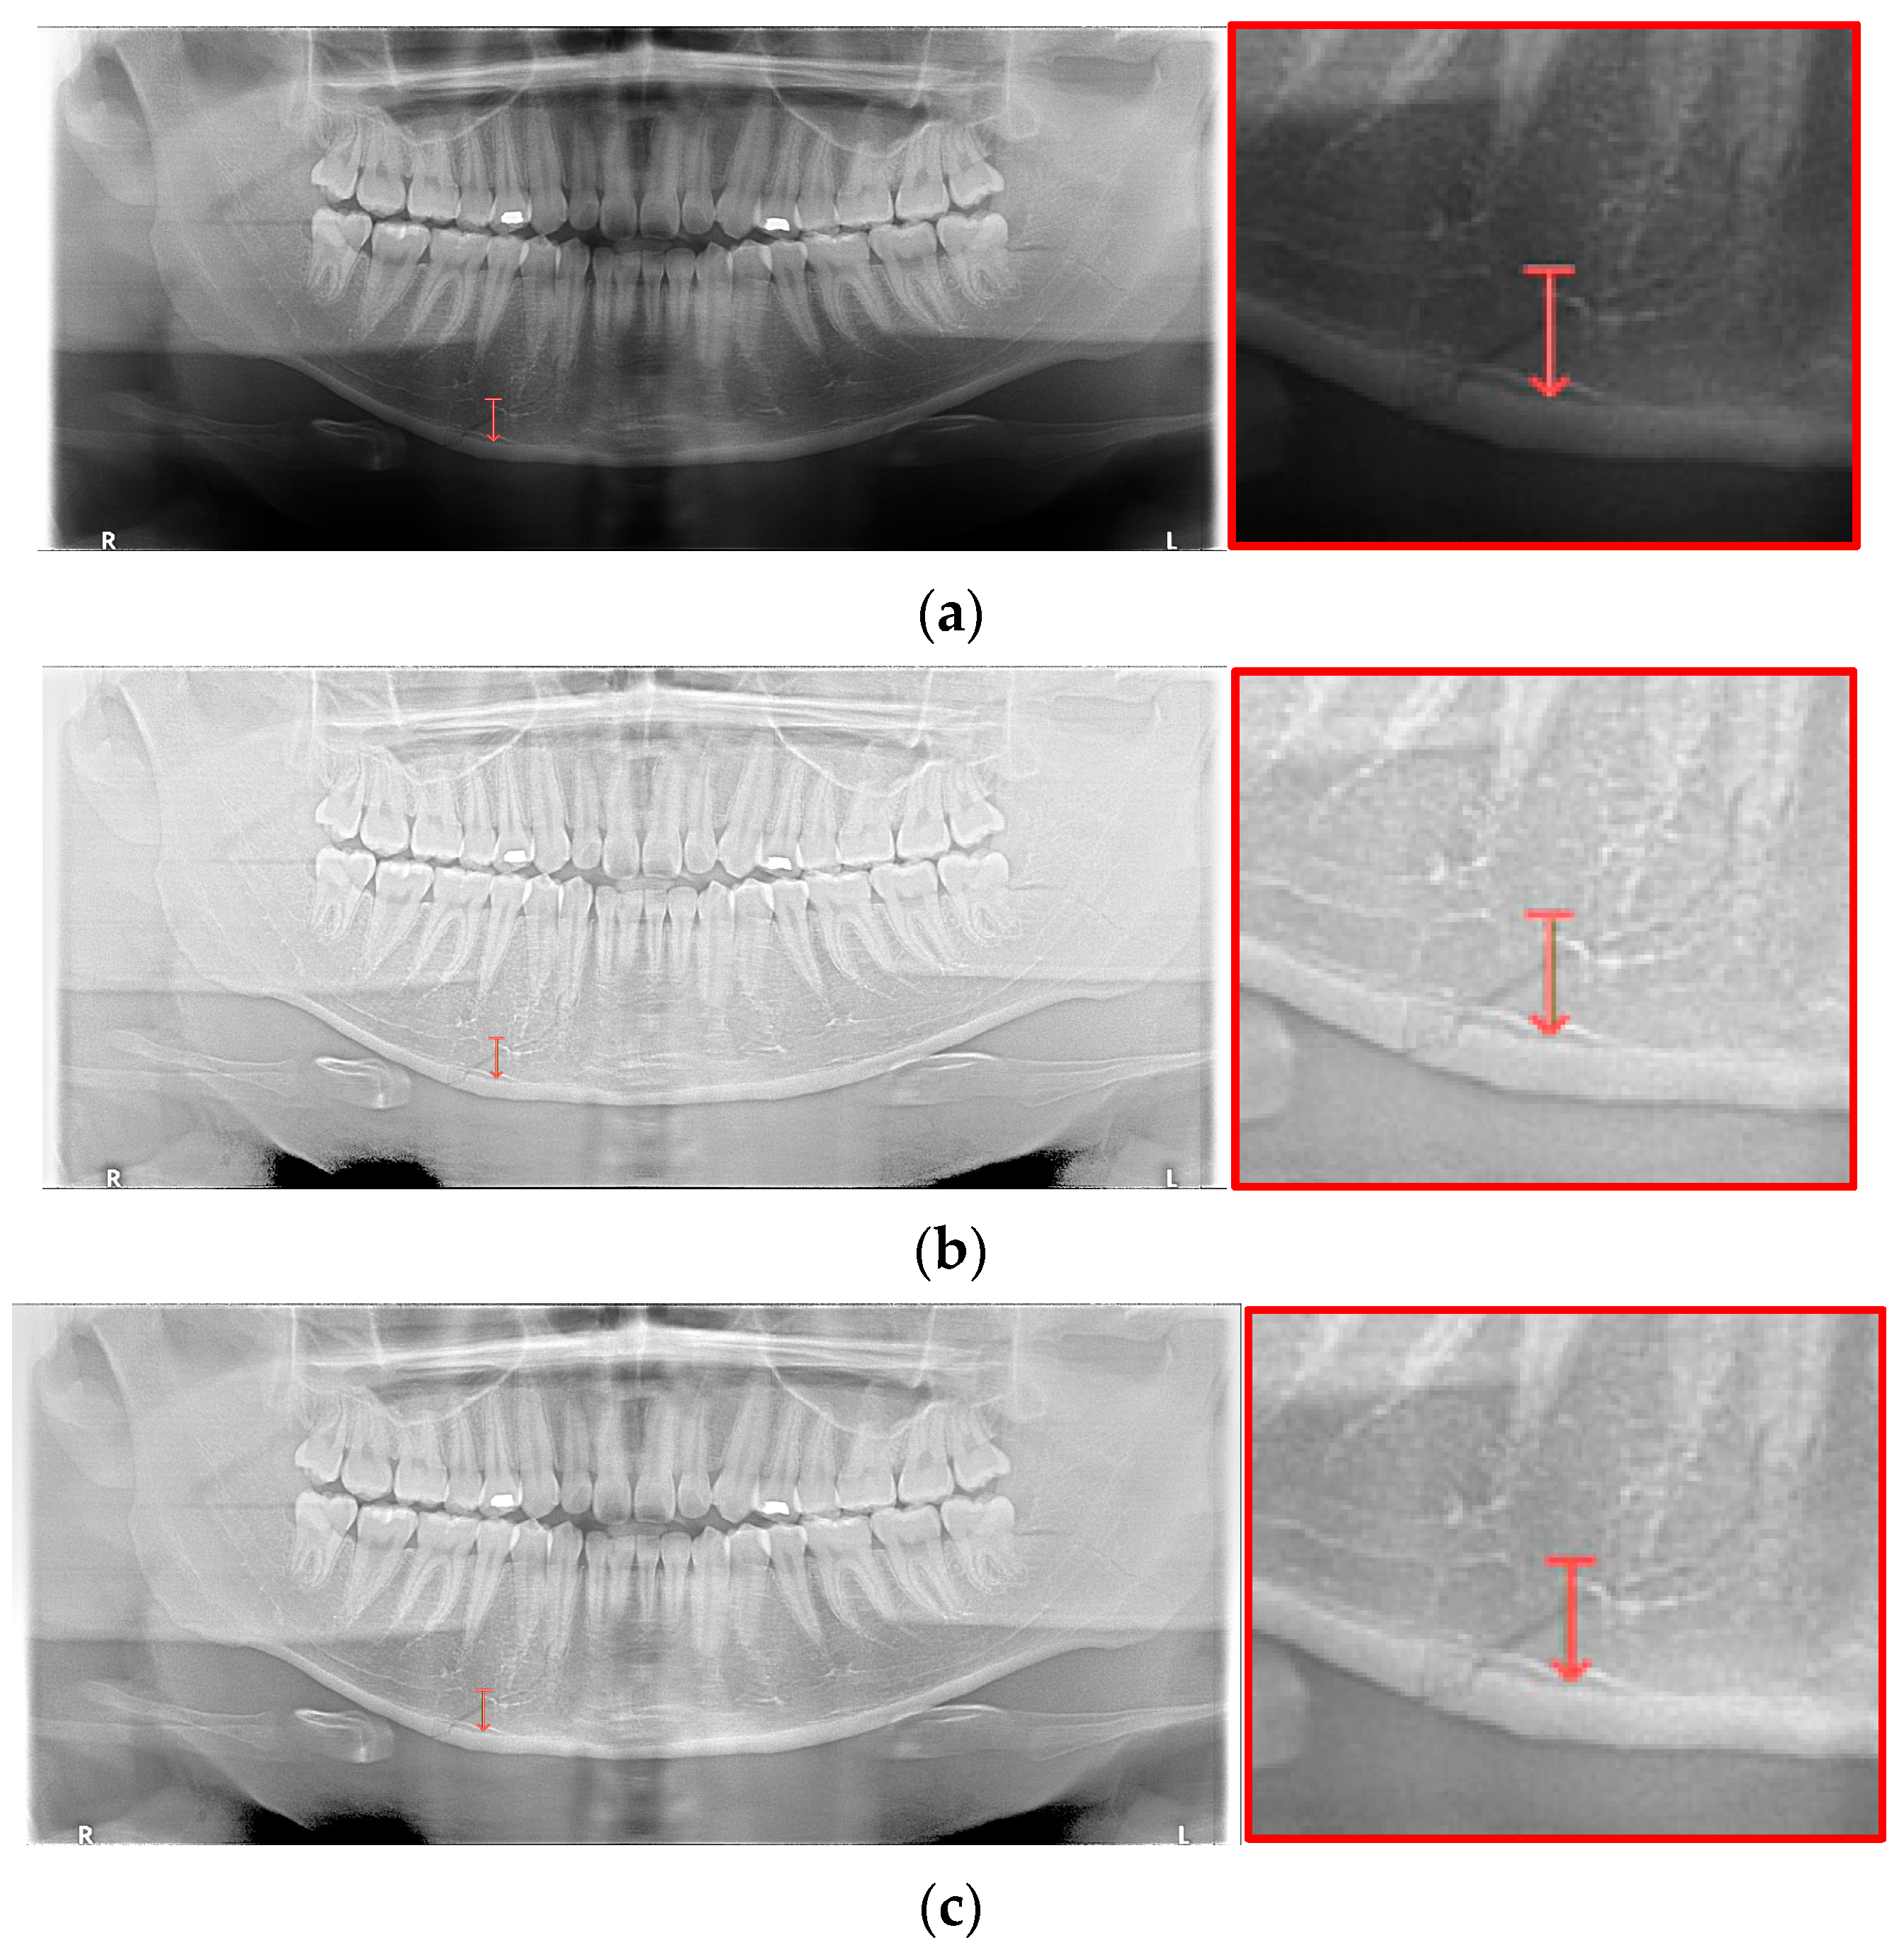

The shape of fractures in the panoramic radiographic image generally shows an oblique fracture with a gap and a shear fracture with a step in red boxes one and two (Figure 2). However, in the condyle region, the fracture shape differs from the general fracture shape, and the bones in the condyle region seem to overlap (dislocation) in red boxes 3 and 4 [7]. Owing to the similarity between the phenomenon that looks like a fracture due to the difference in shading on the panoramic radiographic image and the shape of a specific fracture, such as a fracture in the condyle region, the expert needs to make a careful judgment. Therefore, deep learning methods can help reduce physician errors and support medical diagnoses.

Figure 2.

The shapes of mandibular fractures: (a) oblique fracture on an angle area; (b) shear fracture and severe shear fracture on a symphysis area; and (c) displaced fracture on a condyle area.